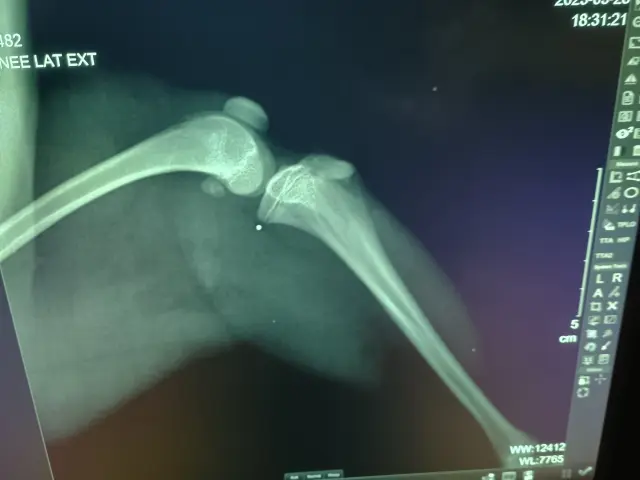

Když k nám přišla, byla vyděšená, nedůvěřivá a úplně ztracená. Dlouhé dny se schovávala pod postelí, krčila se, odmítala kontakt, jídlo i venčení. Při manipulaci dostávala záchvat hysterie a bylo náročné ji uklidnit. Když jsme konečně mohli začít s její postupnou socializací, zjistili jsme ještě něco horšího – Mia měla vážně deformované zadní nohy. Na klinice ji vyšetřil pan ortoped, který i z rentgenových snímků stanovil diagnózu – těžká luxace patel (kolenních čéšek) na obou nohách a vyosené kosti.

Na začátku června podstoupila Mia operaci vyššího stupně luxace pately (čéšky). Na zákaldě rentgenu bylo nejdříve přistoupeno k levému koleni , kde byla již výrazně uzavřená růstová zóna. Pan ortoped situaci vyřešil Imbrikací kloubního pouzdra.